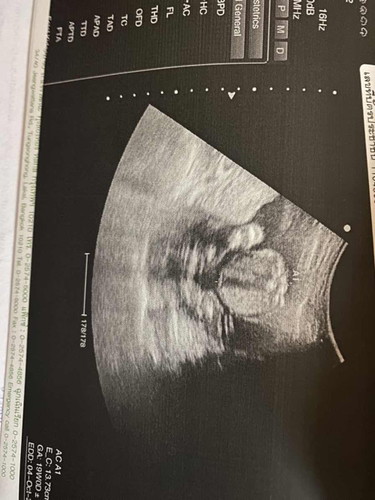

แม่ๆช่วยดูหน่อยค่ะ ว่านี่คือส่วนไหนคะ

น่าจะท้อง+ขาค่ะ กลม ๆ คือพุง